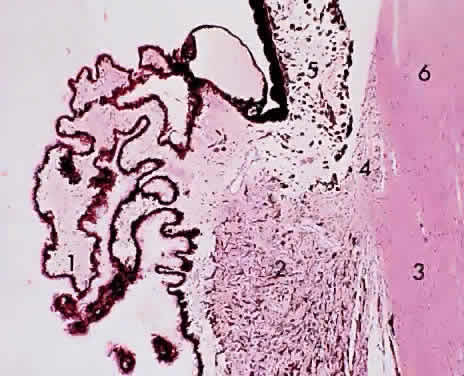

Fig. 10. Ciliary body/pars plicata: 1, ciliary process; 2, ciliary muscle (radial and circular); 3, sclera; 4, anterior chamber angle trabecula; 5, iris; 6, cornea (× 105, KEI 8982B).